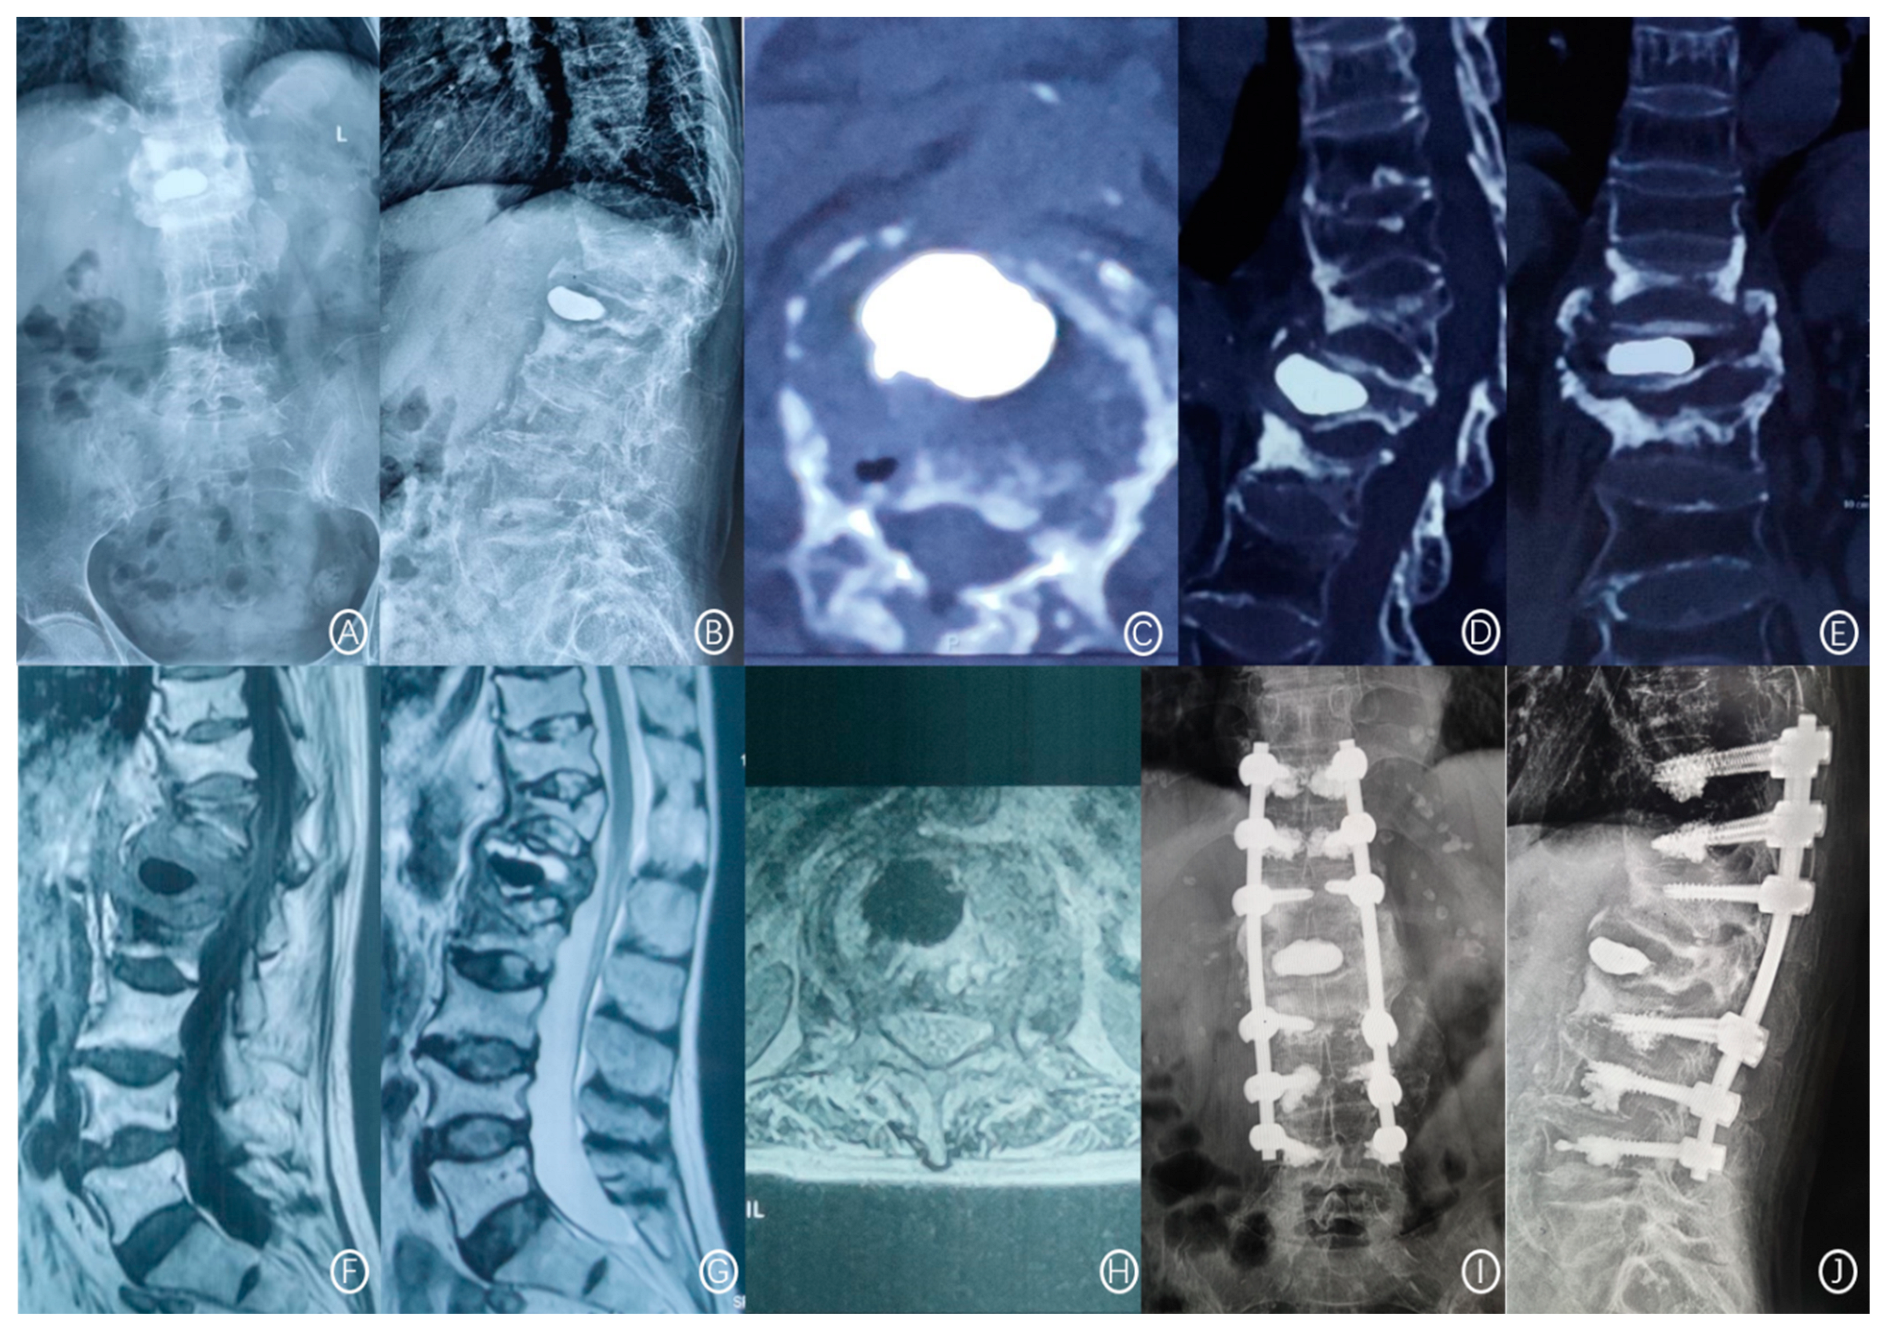

2.3. Treatment Method